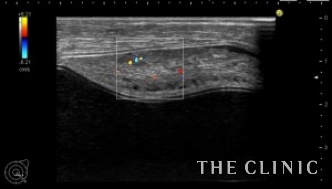

エコー所見です。

右はバッグの破損はありません。左はカプセル拘縮が強くエコーではカプセルとバッグの間に通常見られない組織を認めました。

血流があります。